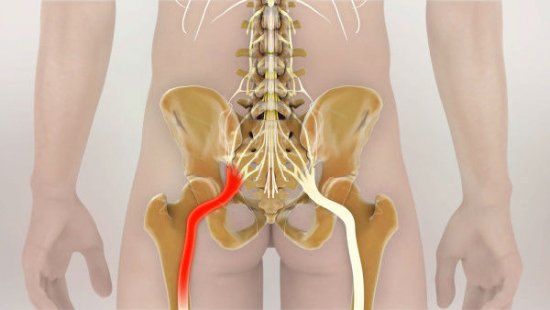

Еще один источник болей в пояснице – наличие межпозвонковых грыж. При их ущемлении, сдавливании нервных корешков возникает довольно сильная, резкая боль, справиться с которой на начальных стадиях помогают стероидные и нестероидные противовоспалительные препараты.

Грыжа позвоночника – частая причина боли

Признаком неблагоприятного исхода является люмбалгия, которая проявляется спектром разнообразных симптомов. Боли по ходу нервного корешка могут отдавать в ягодицы и ступни. Дискомфорт появляется при наклонах (даже при наклоне головы вниз), смехе, кашле и т. д. Болевой синдром усиливается при поднятии лежа на спине прямой ноги.

В большинстве случаев болевые ощущения внизу поясницы появляются в результате защемления спинномозговых нервов, что приводит к острой, или резкой боли. При этом боли сопровождаются не проходящими спазмами спинных мышц. Любые последующие попытки нормально двигаться вызывают лишь усиление боли.